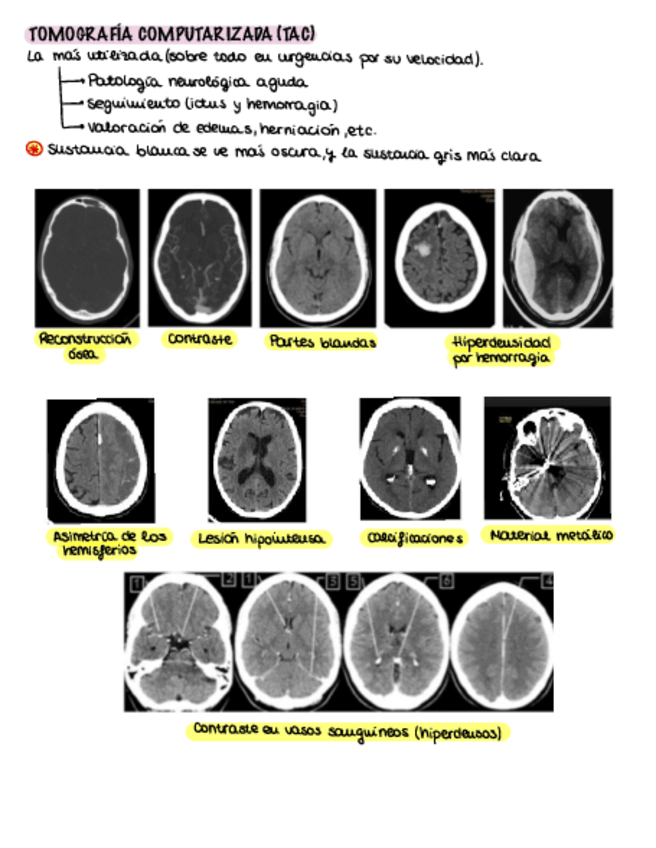

He publicado nuevos apuntes de 3º ESTUDIO POR LA IMAGEN: Apuntes-neuro.pdf

10 páginas